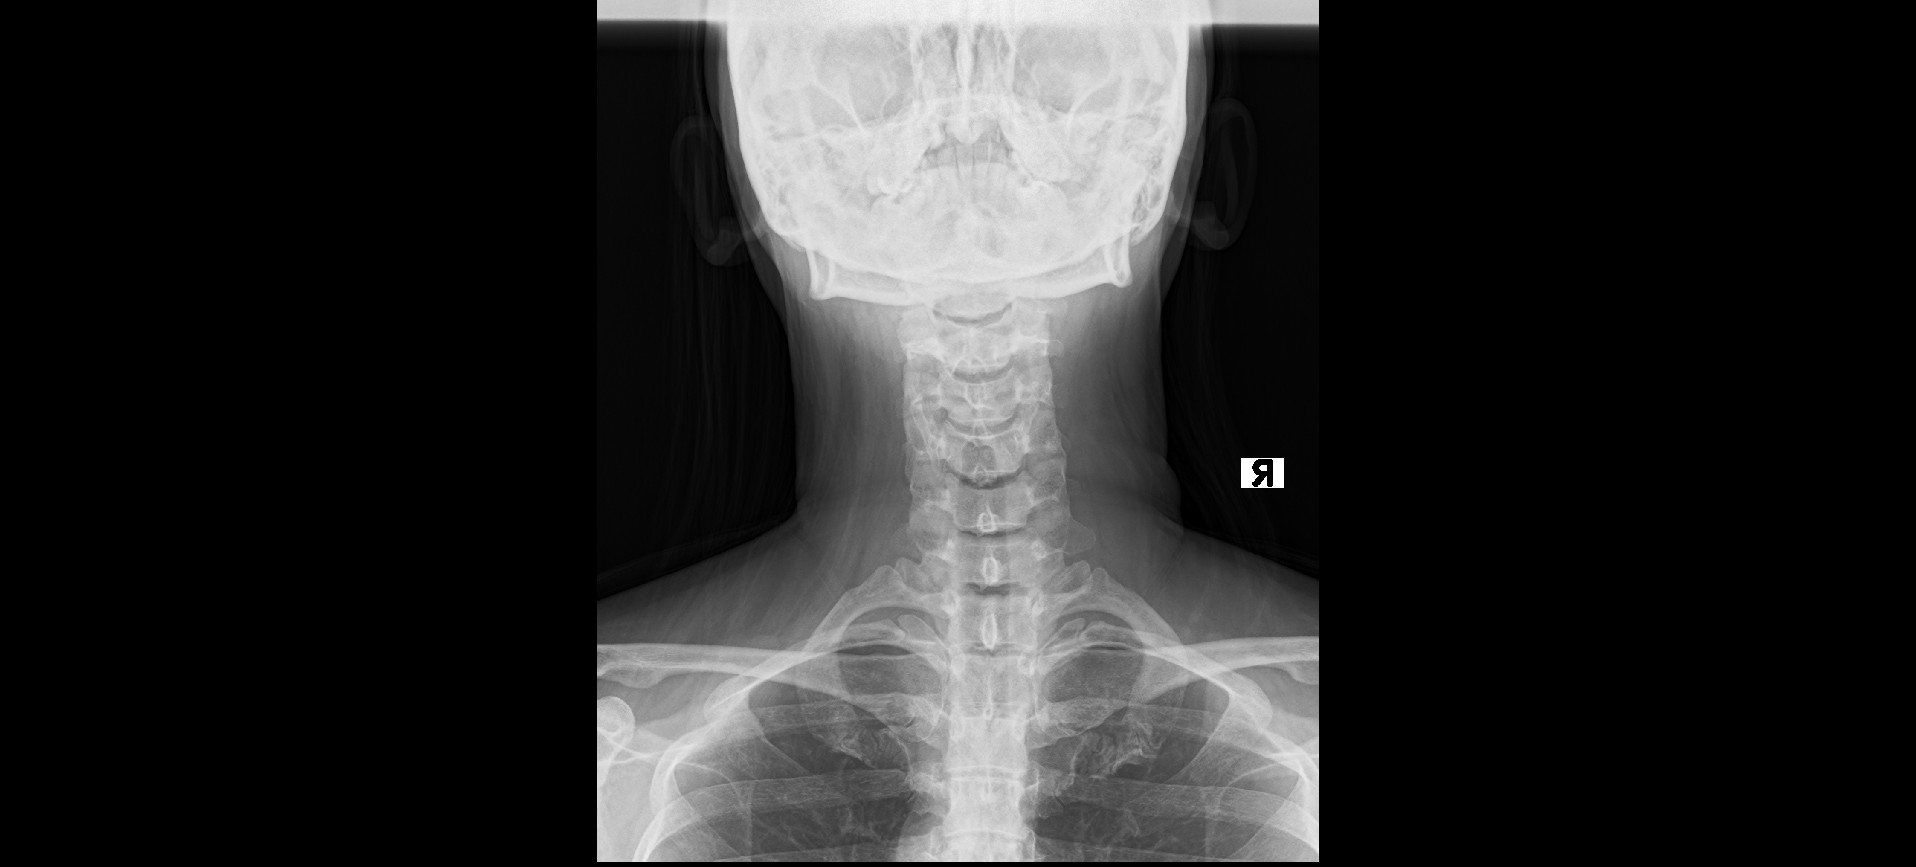

レントゲンでは、ファーガソン角が25度、正常角と比べ減少しており腰椎の前彎が減少している。椎間板はD2~3の変性がみられた。